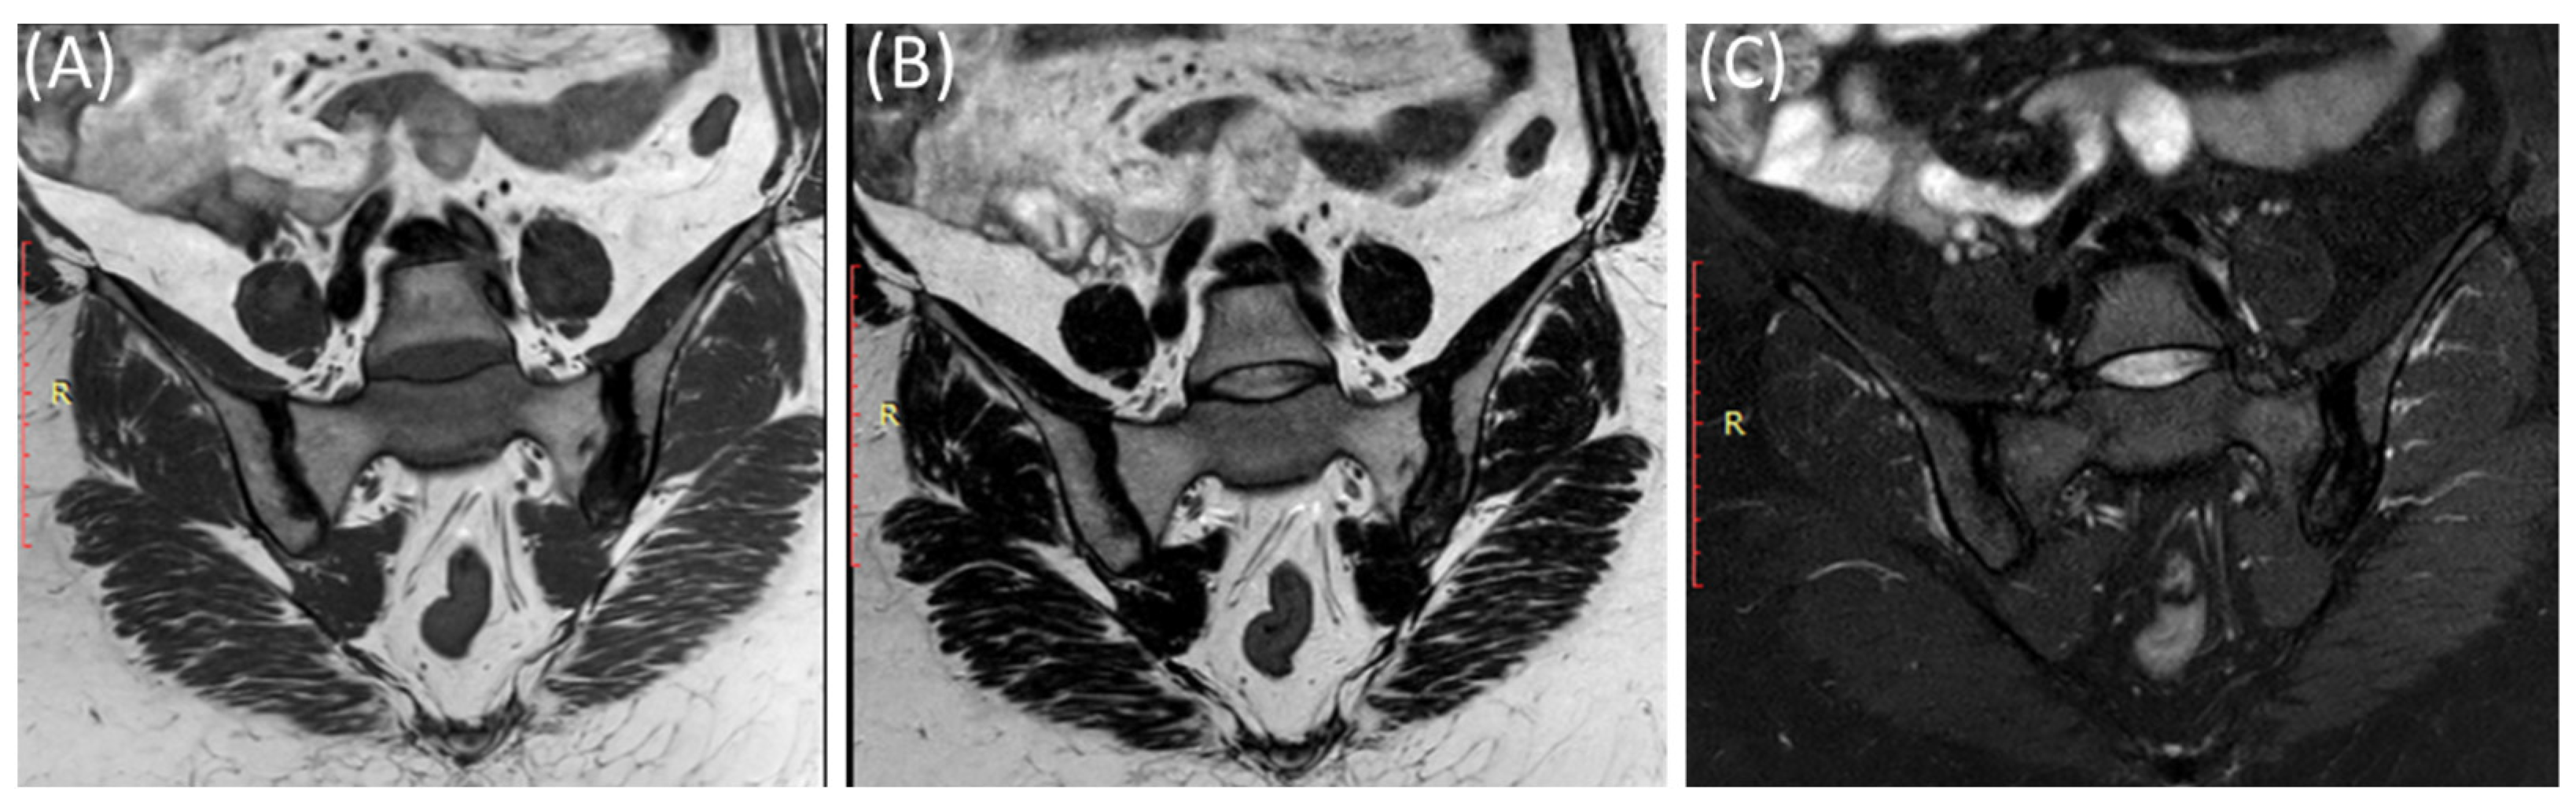

Figure 6.

Coronal T1-WI image (A), coronal T2-WI image (B) and coronal T2-fat suppression image (C) showing sclerosis and mild irregularity in both sacroiliac joints, more on the left side with no evident bone marrow edema in a 52-year-old female with chronic low back and hip pain suggestive of bilateral chronic sacroiliitis.

As shown in Figure 7, fat suppression techniques or fat saturation sequences are often used in MRI to suppress the signal from fat tissue, making it easier to identify areas of inflammation and edema [55,56].